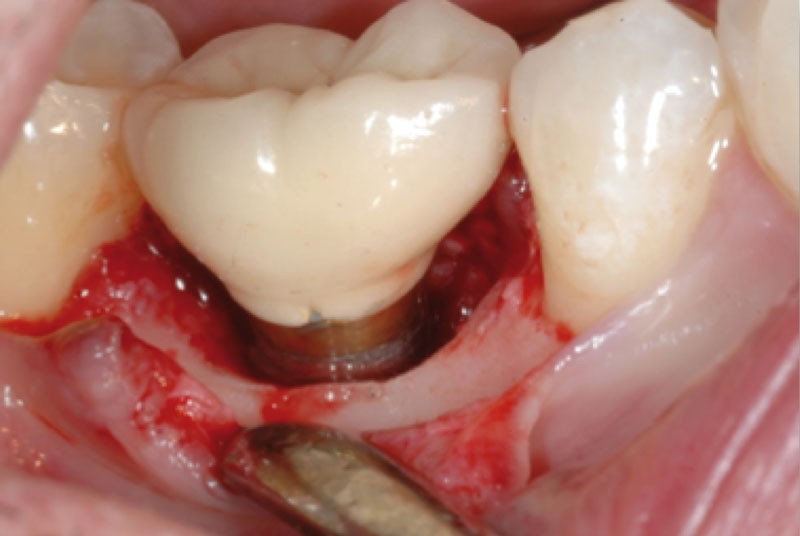

Les mucosites sont des lésions inflammatoires des tissus mous péri-implantaires sans atteinte du tissu osseux (fig. 1).